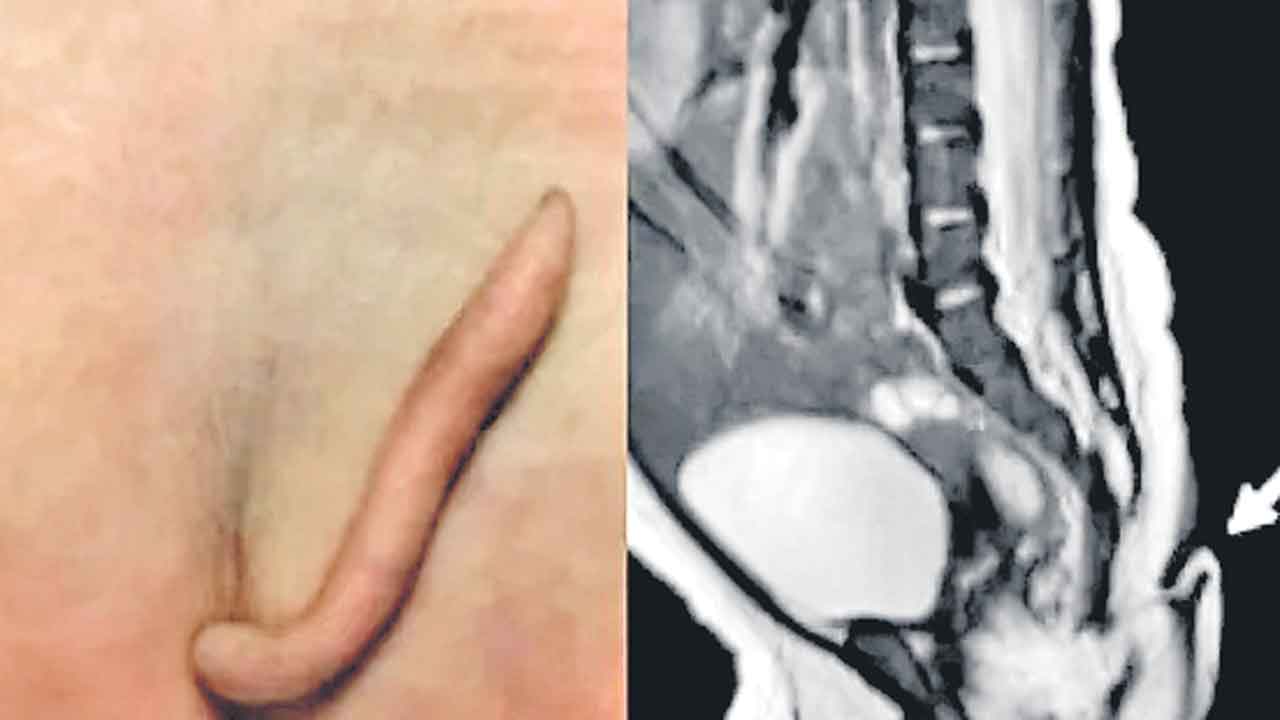

మెక్సికోలో అరుదైన ఘటన చోటుచేసుకొన్నది. ఈశాన్య మెక్సికోలోని న్యూవో లియోన్ దవాఖానలో ఓ ఆడ శిశువు 2 అంగుళాల తోకతో జన్మించింది. మృదువైన చర్మంతో, పదునైన మొన కలిగి 3-5 మిల్లీమీటర్ల వ్యాసార్థంతో ఈ తోక ఉన్నదని వైద్